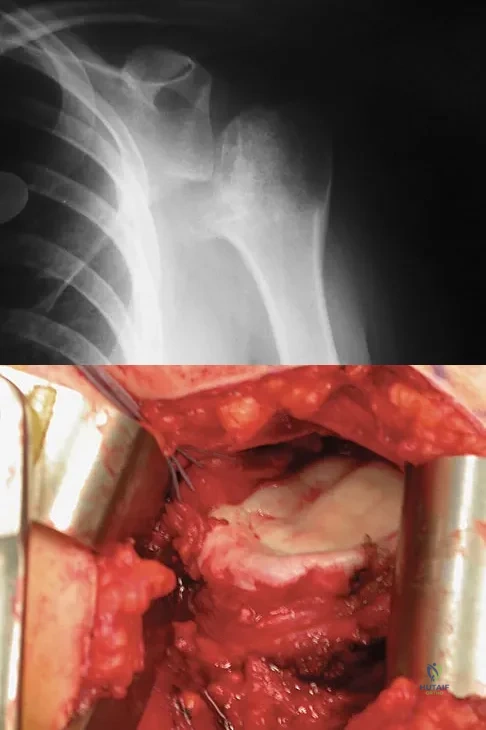

A 28-year-old man sustained a shoulder dislocation 2 years ago. It remained dislocated for 3 weeks and required an open reduction. He now reports constant pain and has only 60 degrees of forward elevation and 10 degrees of external rotation. He desires to return to some sporting activities. An AP radiograph and intraoperative photograph (a view of the humeral head through a deltopectoral approach) are shown in Figures 31a and 31b. What is the best treatment option to decrease pain and improve function?